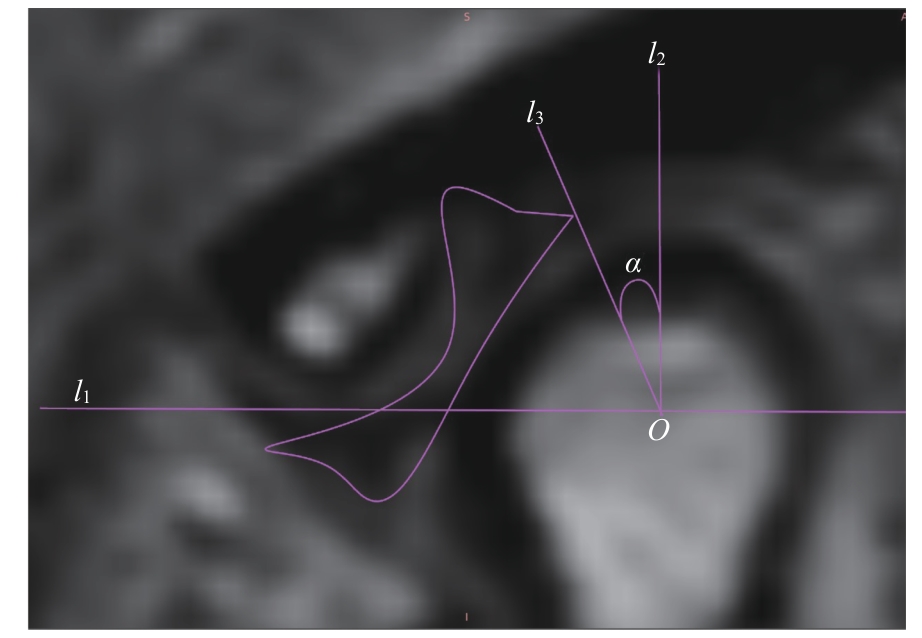

ARAYASANTIPARB R, TSUCHIMOCHI M. Quantification of disc displacement in internal derangement of the temporomandibular joint using magnetic resonance imaging[J]. Odontology, 2010, 98(1): 73-81.

|

| [20] |

YANG Z J, WANG M G, MA Y W, et al. Magnetic resonance imaging (MRI) evaluation for anterior disc displacement of the temporomandibular joint[J]. Med Sci Monit, 2017, 23: 712-718.

ZHANG Q, YE Z, WU Y G, et al. Nonlinear relationship between temporomandibular joint disc displacement distance and disc length: a magnetic resonance imaging analysis[J]. J Clin Med, 2022, 11(23): 7160.